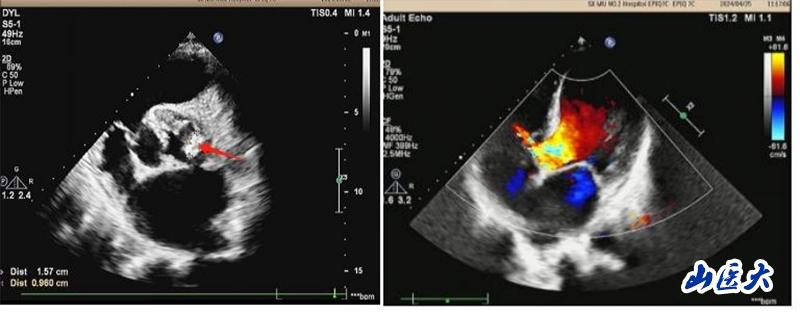

患者系一名中年男性,20余年前在当地医院体检发现心脏杂音,但未进一步诊治。2024年3月初开始间断出现发热、胸闷、气短,体温高达38.5℃,伴咳嗽、咳白色痰液,不能平卧休息,伴双下肢水肿、食欲不振,就诊于万象城第二医院心血管内科。行心脏彩超等辅助检查后诊断为:感染型心内膜炎、主动脉瓣赘生物,主动脉瓣二瓣化畸形伴重度关闭不全,二尖瓣中度关闭不全,室间隔缺损,肺动脉高压。布氏杆菌感染进一步加重了心功能衰竭。心血管内科周荣副主任医师为其制定了精细的治疗方案,给予抗感染、利尿等多种措施治疗后,患者上述症状稍缓解,但须手术治疗方能彻底痊愈。

患者转入心胸外科后,马捷主任医师根据患者病史长、心功能差、合并多个瓣膜病变和长期心内分流畸形的病情特点,为其制定了个体化的诊疗方案,积极调整患者心、肺功能,改善营养状态,创造手术机会。5月14日,马捷主任医师、李强副教授团队在麻醉科、手术室等多学科的密切配合下,为患者成功实施了心脏手术:切除病变的主动脉瓣、植入主动脉机械瓣、行室间隔缺损修补术以及二尖瓣成形术。经过医护团队的不懈努力,以及患者和家属的积极配合,患者经受住了复杂心脏手术的风险,终获新生,体力、睡眠和食欲都恢复到正常人的水平,心脏恶液质得以逆转,目前即将痊愈出院。术后复查心脏超声,各瓣膜功能恢复良好。